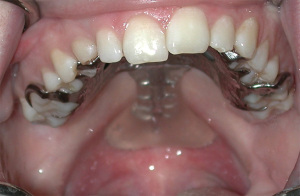

Removable dental prosthesis and complete denture

A removable dental prosthesis or complete denture is indicated when several or all teeth are missing and particularly when there are tissue deficiencies, fistulas and loss of alveolar ridge or proper contour of the hard palate. The base and flange of the denture can compensate for unfavorable size and shape of the alveolar ridge and hard palate allowing proper teeth arrangement and facilitating improved speech (4). Moreover, in cases with severe vertical bone loss, a denture can prevent hygiene problems and can provide improved esthetics compared to a fixed prosthesis, for example by providing labial support.

Removable dental prostheses or complete dentures are one of the primary prosthodontic oral rehabilitation treatments for cleft lip and palate (5). Although the types of prosthesis offered to cleft lip and palate individuals are similar to non-cleft individuals, there are differences between cleft individuals and non-cleft individuals, especially regarding implant-supported prostheses. Level of bones around cleft area might be lower due to anatomic defects, delayed teeth eruption, malpositioned teeth, and presence of prostheses. Removable prostheses offer distinct advantages in covering and restoring alveolar deformities and defects in addition to replacing missing teeth and facilitating oral hygiene.

There are several oral manifestations of ectodermal dysplasia, for example hypodontia and anodontia, underdeveloped alveolar bone, impacted teeth and malformed teeth such as peg-shaped teeth. The prosthodontic treatment, which can be prescribed at various ages, includes removable dental prosthesis, onlay, tooth- and implant-supported fixed dental prosthesis and crown (6). A recent consensus on management of children with dental manifestations of ectodermal dysplasia concluded that for hypodontia and anodontia, no treatment is needed until the age of two (7). However, in order to minimize orofacial impairment with regards to nutrition, speech and esthetics, the first prosthetic rehabilitation should be performed before school enrolment (8).

As the pediatric patient grows, ensuring fit of the prosthesis through time is a challenge. Use of interim all acrylic instead of a definitive (chrome cobalt) removable dental prosthesis is preferred as these can be easily relined, rebased and remade with patient growth to maintain oral functions such as speech, mastication and swallowing (9). Due to growth, renewal of complete dentures or overdentures is expected every one to three years and for removable partial dentures after one to six years (8).

For anodontia, at age two to six years, it is agreed that the treatment of choice is a maxillary complete denture. The consensus regarding ectodermal dysplasia states that at 14 years of age, patients with anodontia secondary to ectodermal dysplasia can be treated with maxillary and mandibular complete denture with or without dental implants to assist with retention and support or an implant-supported fixed (complete denture or metal ceramic) prostheses (7).